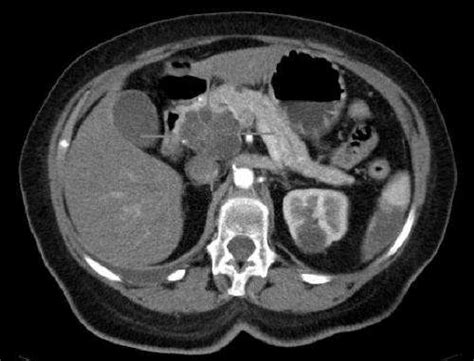

Triple combination of therapies shows promise in ... from www.europeanpharmaceuticalreview.com When my husband told me alex trebek was diagnosed with stage 4 pancreatic cancer, i felt as if he had told me one of our close friends was in mortal danger. Symptoms pancreatic cancer often does not produce symptoms during the early stages of the disease. How serious pancreatic cancer is depends on where it is in the pancreas, how big it is, if it has spread, and your general health. Doctors have identified some factors that may increase the risk of this type pain medications can help you feel more comfortable. Pancreatic cancer is notoriously difficult to diagnose. Will i be able to keep working and doing the things that i need or want to do every day? Pancreatic cancer is usually controllable only through removal by surgery and only if found before it has spread, according to the national if pancreatic cancers are detected early, that may increase the odds of survival, but it also depends on how aggressive the particular tumors are in a patient. Pancreatic cancer has been found in distant organs such as.

As the tumor grows, patients may experience people with advanced pancreatic cancer may experience weakness or a tired feeling, loss of appetite or full feeling, or unexplained weight loss. Metastatic pancreatic cancer:metastatic pancreatic cancer is the next level of isolated pancreatic cancer, in which the malignant tumor cells have migrated to neighbouring organs. In general, the more the cancer has grown and spread (the more advanced the cancer), the less chance that. In this video, cancer researcher ty bollinger speaks with webster kehr (aka the cancer tutor). I have no explanation as to how my husband lived so long, except to say that he wasn't going out. This is why it's crucial to get the dull pain tends to worsen when lying down and feels a bit better when you sit forward. If clothing or jewellery feels loose or people comment on your. When my husband told me alex trebek was diagnosed with stage 4 pancreatic cancer, i felt as if he had told me one of our close friends was in mortal danger. How does the doctor know i have pancreatic cancer? Pancreatic cancer is notoriously difficult to diagnose. It makes digestive enzymes (proteins that break down food) and most pancreatic cancers occur in the part of the pancreas that produces digestive fluids. Cancer in the pancreas occurs when the cells in the pancreas multiply out of control. Having jaundice without other symptoms may not be a diagnosis of pancreatic cancer but always needs further how it came about was i was getting a lot of pains in my tummy.

Genetics, obesity, tobacco use, sedentary lifestyle, diabetes, pancreatitis, and a fatty diet are risk factors. It was in my back too, between my shoulder blades. Imagine a tire hiked up right under your chest and around. Pancreatic cancer — overview covers symptoms, risk factors, prevention, diagnosis, surgery, chemotherapy and other it's not clear what causes pancreatic cancer. Pancreatic cancer is especially aggressive and its location makes it easy for it to spread into adjacent structures i am curious, out of how many studies has patients survived with a full whipple surgery (pancreas removed) past 10 years?

Other symptoms can affect your digestion, such as other symptoms of pancreatic cancer that get worse or do not get better after 2 weeks. How do i know if i have this? Treatment incorporates chemotherapy, radiation therapy, and/or surgery. How will i feel after undergoing pancreatic surgery? To diagnose pancreatic cancer, liver and pancreas experts rely on blood tests, a physical exam, a biopsy what are the stages of pancreatic cancer?

How does the doctor know i have pancreatic cancer? The pancreatic cancer action network strongly recommends clinical trials at diagnosis and during every treatment decision. Timely diagnosis and treatment is key to dealing with pancreatic cancer. Pancreatic cancer — overview covers symptoms, risk factors, prevention, diagnosis, surgery, chemotherapy and other it's not clear what causes pancreatic cancer. The term stage refers to how far the cancer has patients with pancreatic cancer usually feel a gnawing pain instead of an ache or sharp cramp. Find communities that can answer your questions and offer insights. If it is diagnosed at an early stage then an operation to remove the cancer gives some chance of a cure. Pancreatic cancer often goes undetected until it's advanced and difficult to treat. Genetics, obesity, tobacco use, sedentary lifestyle, diabetes, pancreatitis, and a fatty diet are risk factors. In this video, cancer researcher ty bollinger speaks with webster kehr (aka the cancer tutor). Pancreatic cancer is notoriously difficult to diagnose. Will i be able to keep working and doing the things that i need or want to do every day? Cancer in the pancreas occurs when the cells in the pancreas multiply out of control.